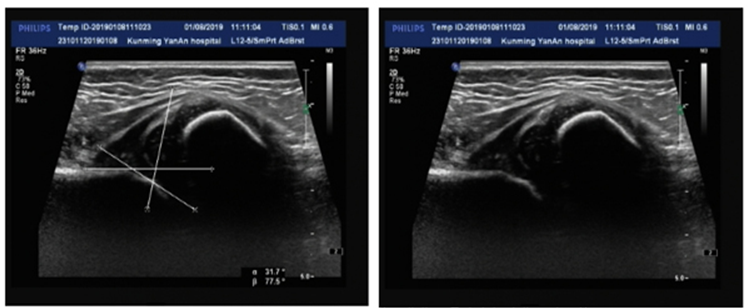

小儿髋关节脱位超声图像

(内收屈曲位股骨头大部分位于髋臼外)